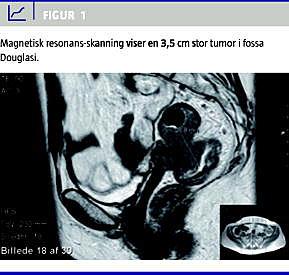

Denne sygehistorie omhandler en 58-årig kvinde, der tidligere var hysterektomeret og ooforektomeret for en benign lidelse, og som igennem to måneder havde haft vekslende afføringsmønstre og intermitterende friskt blod med afføringen. Der var intet vægttab eller vaginal blødning, men dysuri og hyppige vandladninger. Ved rektal- og vaginal eksploration fandtes en fast, mobil knytnævestor tumor i fossa Douglasi. Der fandtes ingen abnormiteter ved vaginal inspektion, og ved sigmoideoskopi var der en stenose 10 cm fra anus, som ikke kunne passeres. Der sås ingen synlige slimhindeforandringer. Vaginal ultralydskanning og magnetisk resonans-skanning viste en tumor i fossa Douglasi med indvækst i vagina og rectum uden tegn på lokal spredning eller fjernmetastaser (Figur 1 ).